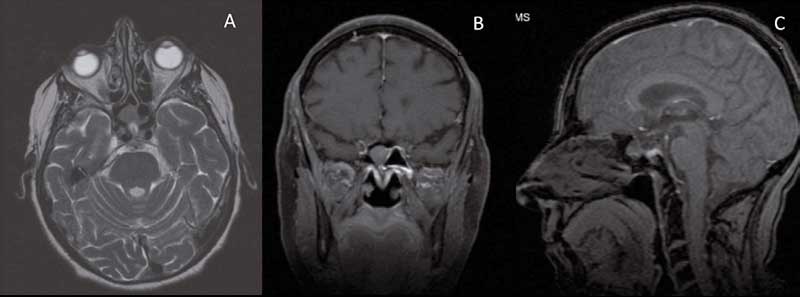

Posteriormente, la resonancia magnética (RM) muestra una silla turca “parcialmente vacía”, elongación de la carótida interna derecha en el segmento cavernoso, y por delante de la elongación y de la silla turca, una formación nodular de partes blandas, isointensa en T1 y T2, de 13x10x10 mm. Su morfología es regular, estructura homogénea y se realza también de forma homogénea tras la inyección del contraste, con una base de implantación sobre el tabique interesfenoidal y crecimiento en el interior del seno esfenoidal derecho sin extensión hacia la silla turca ni senos cavernosos (Figura 1). Se decide resección endoscópica nasosinusal de la lesión realizando previa esfeinoidotomía.

Figura 1: Resonancia magnética de senos paranasales con contraste. En corte axial (1A) se observa formación nodular, isointensa en T1 con el parénquima cerebral,

situada por delante de elongación de la arteria carótida derecha y de la silla turca. También se observa en corte coronal (1B), con base de implantación sobre el

tabique interesfenoidal y sin extensión a senos cavernosos, así como en corte sagital (1C), presentando crecimiento en el interior del seno esfenoidal derecho. El diagnóstico anatomopatológico fue de adenoma hipofisario ectópico, de 12 mm, que contactaba con bordes y con inmunohistoquímica positiva frente a prolactina y HGh- GH, además de a CKAE1-AE, CK8/18, CD56, cromogranina y sinaptofisina.